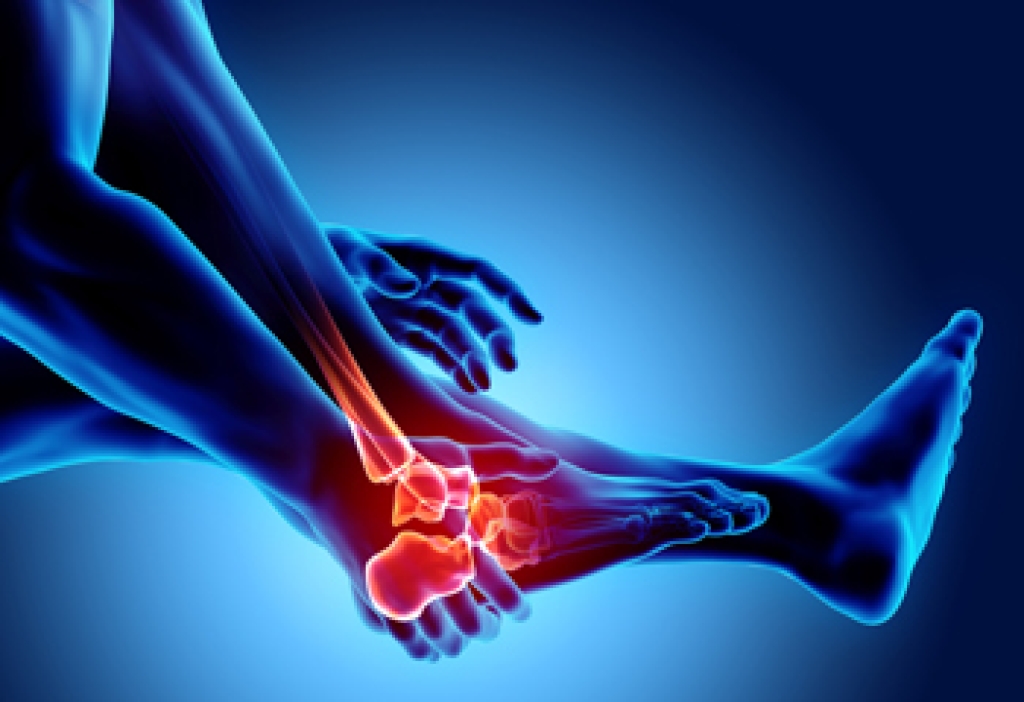

If your feet feel like they are burning up, it may be a sign that you have experienced nerve damage in the foot or leg, an injury, or a compression of the nerves. Burning feet, also known as Grierson-Gopalan Syndrome, is a condition that consists of damage to the small nerve fibers of the foot. Although the cause of this condition is not clear, it is often found in people who have diabetes, vitamin B deficiency, or rheumatoid arthritis. Among other possible causes of burning feet are peripheral artery disease, peripheral neuropathy, and Morton’s neuroma. Other factors that can result in burning foot syndrome include kidney or thyroid problems and abnormal biomechanics of the foot. Common symptoms of burning foot syndrome are a pain in the soles of the feet, a feeling of pins and needles, and numbness. If you regularly experience such symptoms, please contact a podiatrist for an exam and a diagnosis, followed by suggested treatment options.

- Injury (from stress fractures, broken toe, foot, ankle, Achilles tendon ruptures, and sprains)

To figure out the cause of foot pain, podiatrists utilize several different methods. This can range from simple visual inspections and sensation tests to X-rays and MRI scans. Prior medical history, family medical history, and any recent physical traumatic events will all be taken into consideration for a proper diagnosis.